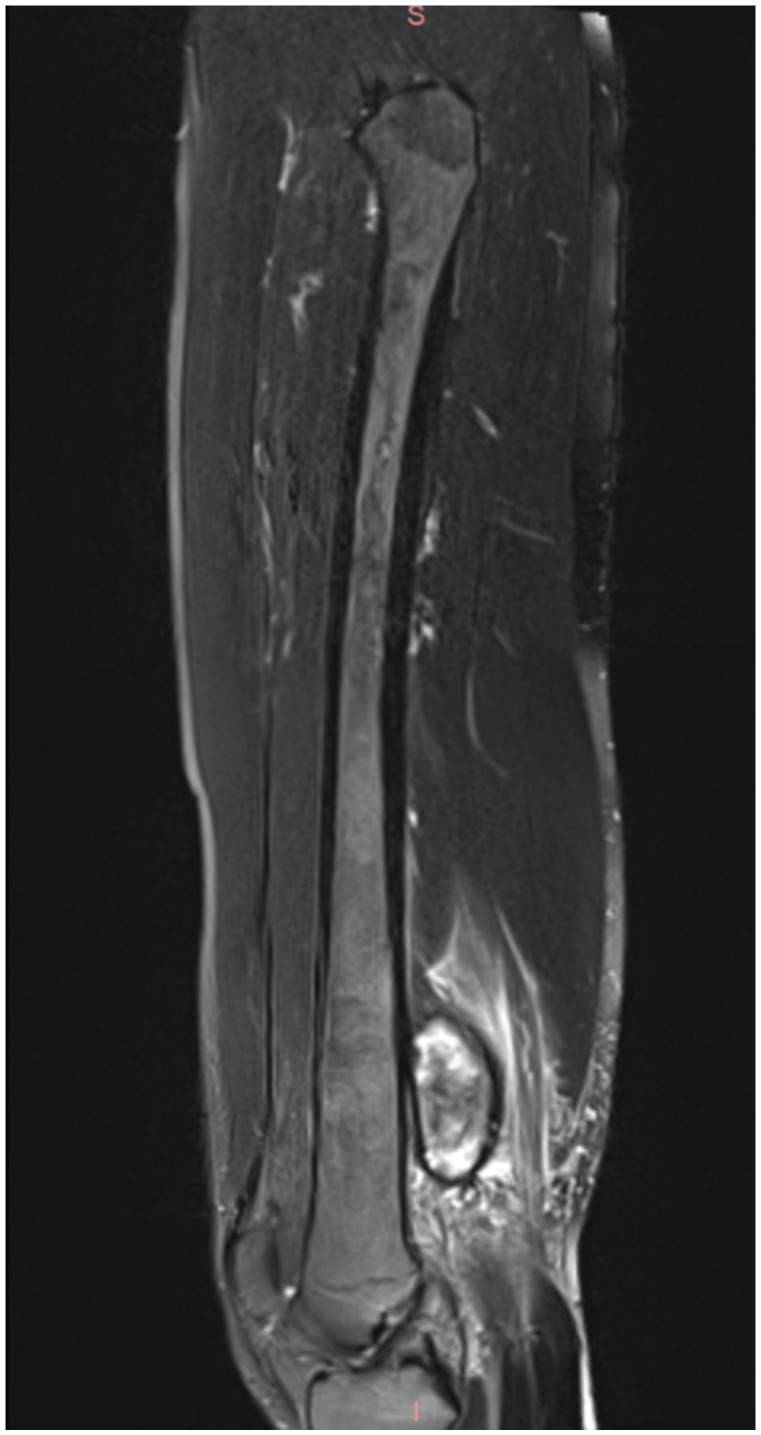

Pseudoaneurysm of the Superficial Femoral Artery Secondary to Exostosis-like Lesion Trauma After Hamstring Tear: A Case Report.